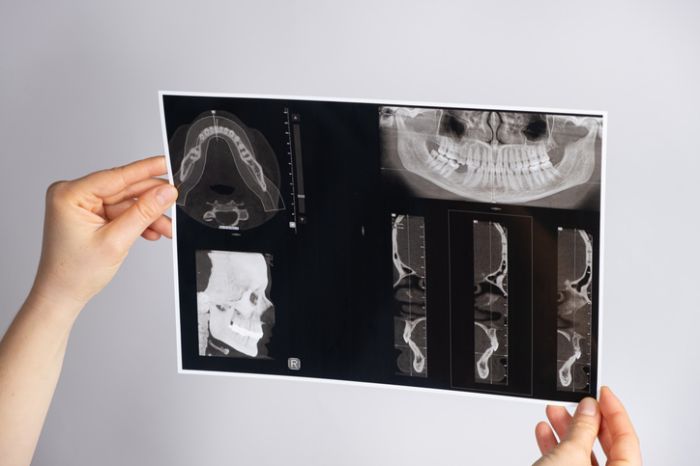

Nach einem Zahnverlust bildet sich der Kieferknochen in der betroffenen Region langsam zurück. Das kann dazu führen, dass für ein stabiles Zahnimplantat nicht mehr genügend Knochensubstanz vorhanden ist. In solchen Fällen ist ein Knochenaufbau sinnvoll – um die natürliche Basis für eine sichere, langfristige Implantatversorgung wiederherzustellen.

Wenn im Oberkiefer zu wenig Knochensubstanz im Bereich der Nebenhöhle vorhanden ist, kann diese durch einen sogenannten Sinuslift schonend wieder aufgebaut werden.